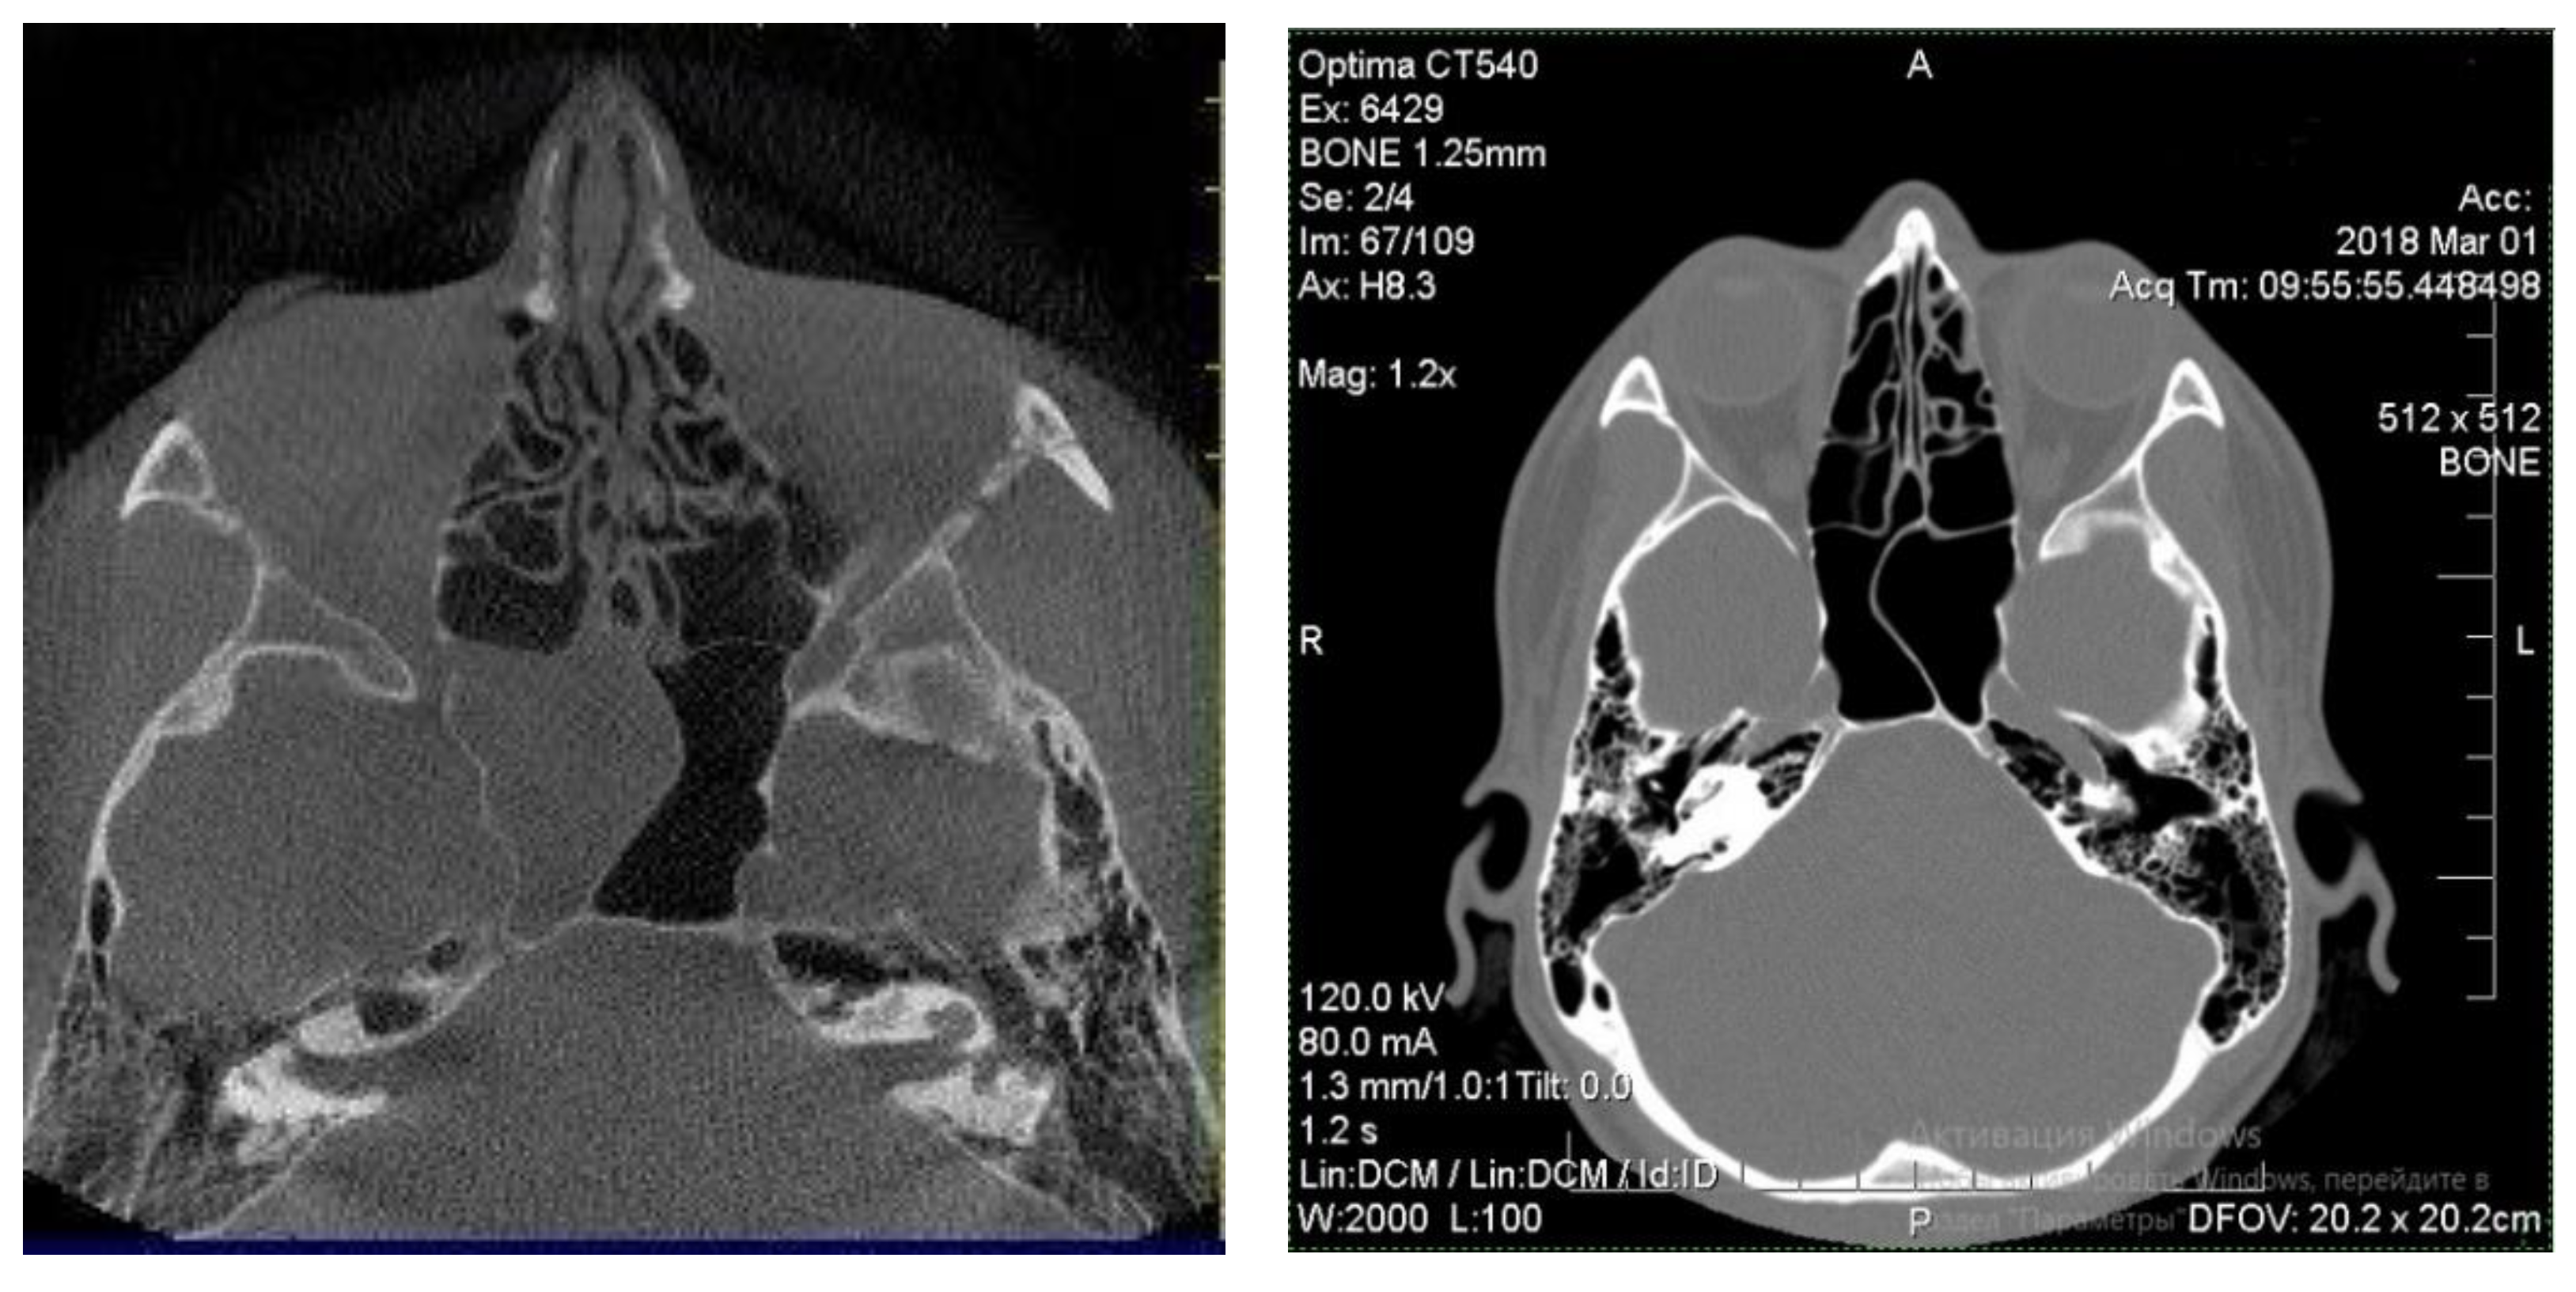

Patients with good outcomes after the treatment, which included residual edematous changes of the sinus mucosa on the CT scan, were designated as group 1 of the study (Figure 2) [18]. This group included 22 patients aged from 6 to 68 years old.

Figure 2.

CT-scan of a patient, who showed good outcomes after conservative treatment and was added to group 1.